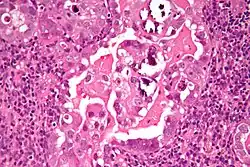

| Histology H&E of uterine serous papillary carcinoma. H&E stain. | |

Histopathologically, uterine serous carcinomas is typically characterized by (1) nipple-shaped structures (papillae) with fibrovascular cores (2) marked nuclear atypia (irregularities in the nuclear membrane, enlarged nuclear size), (3) psammoma bodies and (4) cilia. These are general findings in serous tumors which are also seen in such tumors in other anatomic locations.